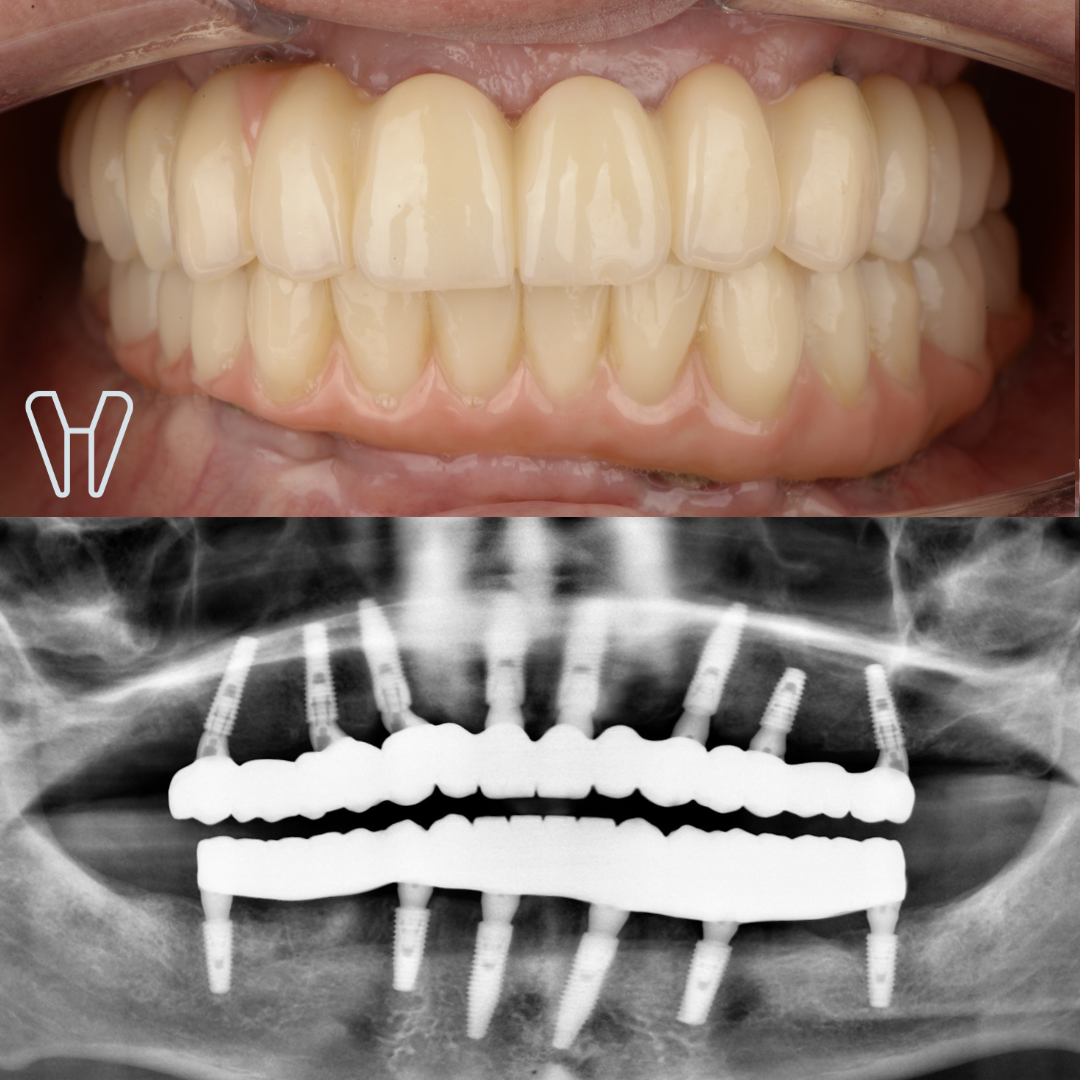

Повна двощелепна реабілітація на імплантатах

Олександр, 53 роки

Втрата зубів та кісткової тканини навколо зубів, в результаті захворювання ясен - парадонтиту. Порушення функції, естетики та якості життя.